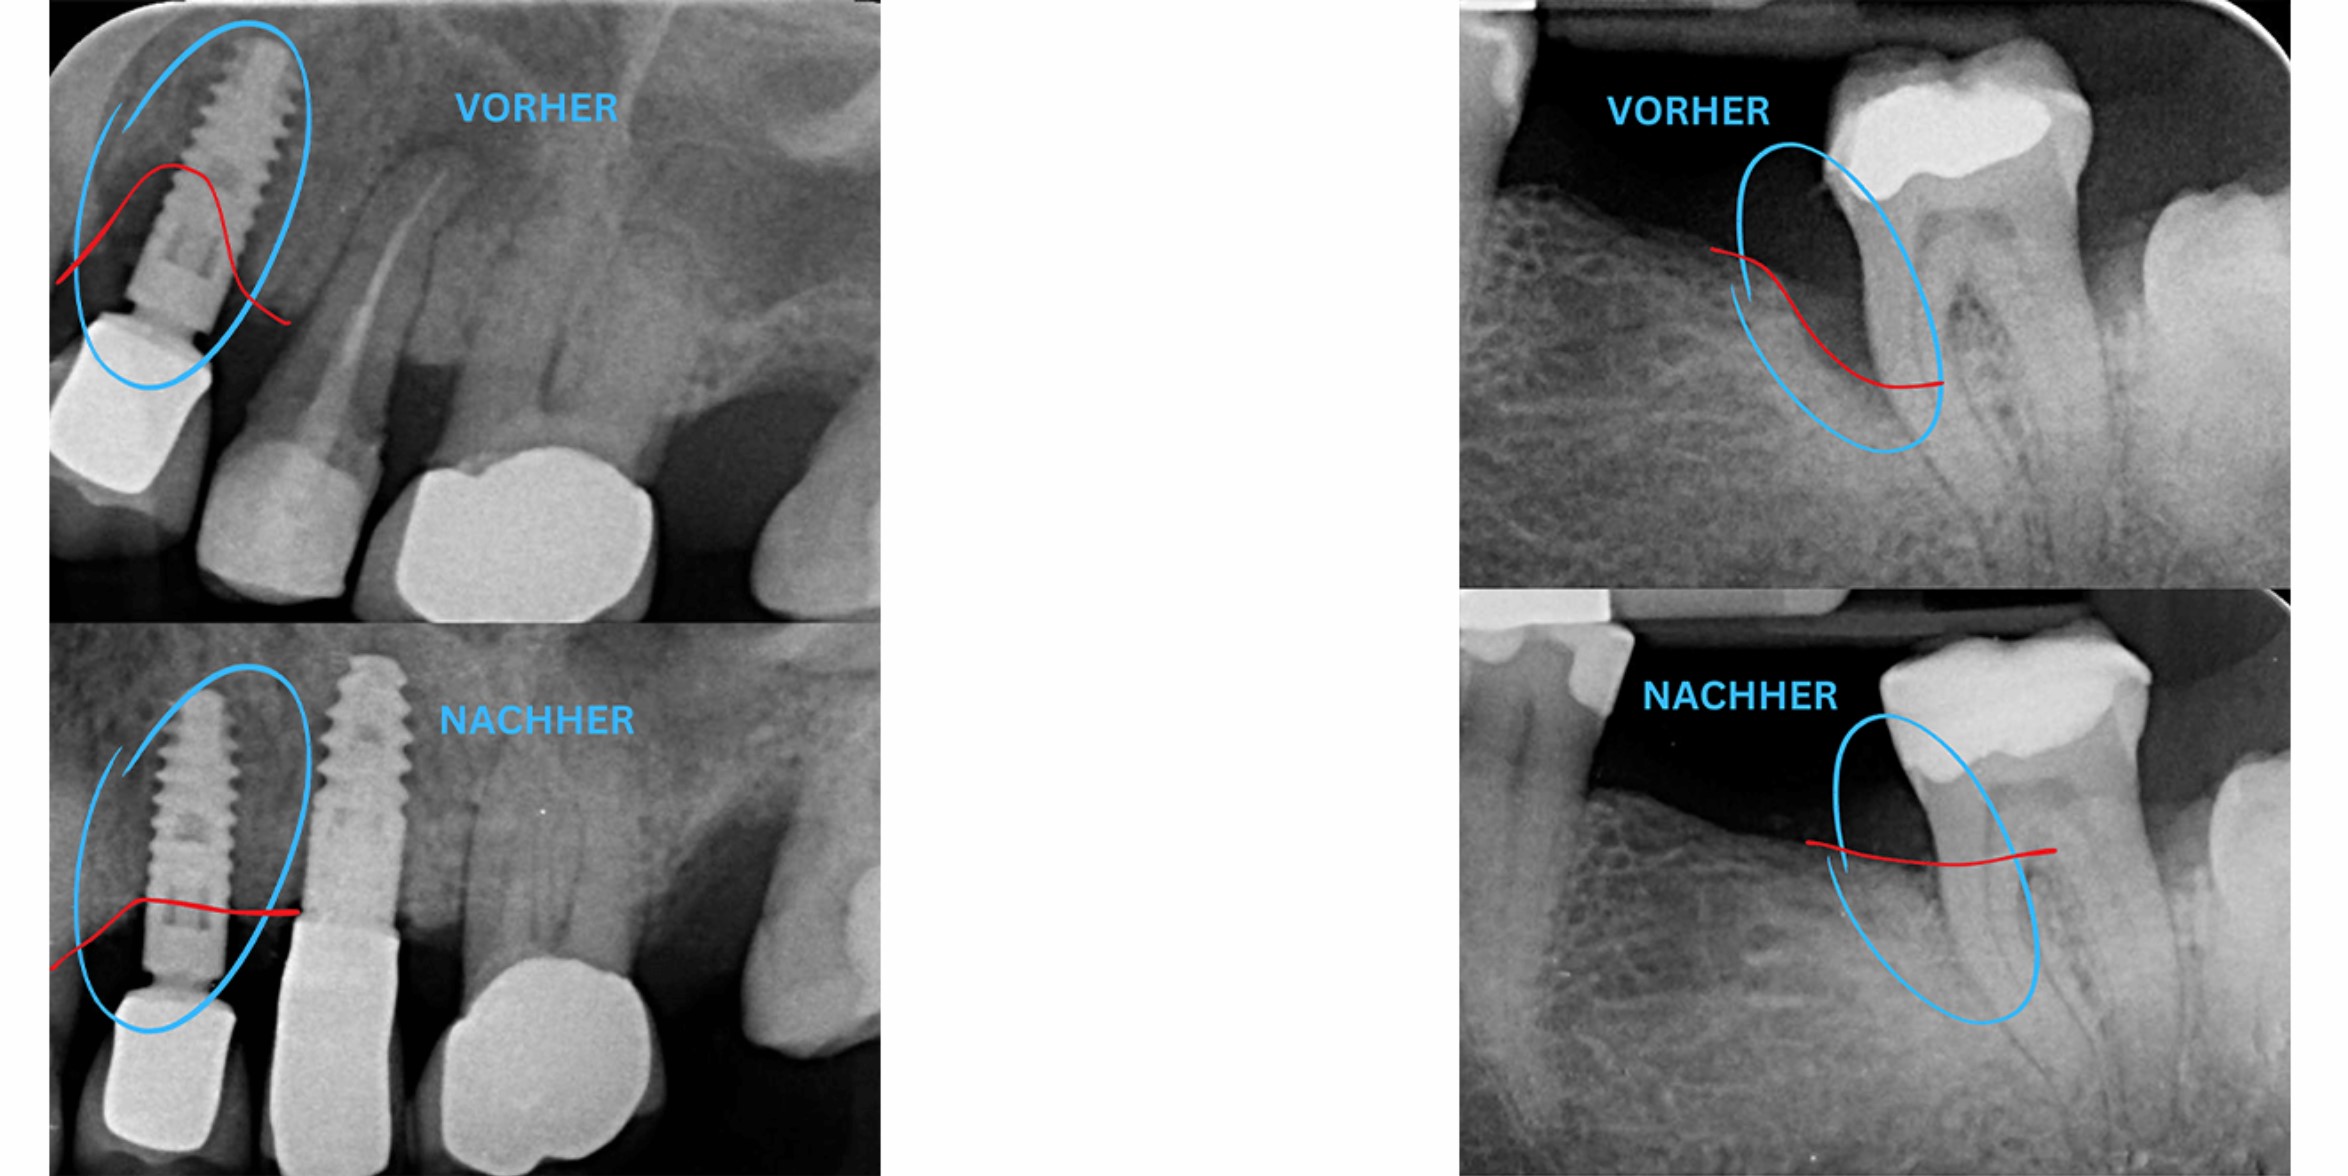

Peri-implantitis is a serious condition that can lead to bone loss around dental implants as a result of an inflammatory reaction. This process often progresses painlessly and chronically, meaning it may remain unnoticed by patients for a long time. The main cause of peri-implantitis is usually a biofilm formed by bacteria on the implant surface beneath the gums. If left untreated, this condition can eventually lead to the loss of the implant.

Our specialized techniques for removing the biofilm allow us to effectively stop the inflammatory process around the implant. In many cases, we are even able to restore lost bone using advanced regenerative procedures. For more severe cases, we also offer removal and replacement of the affected implant.

• In many cases, previously lost bone substance can be restored.